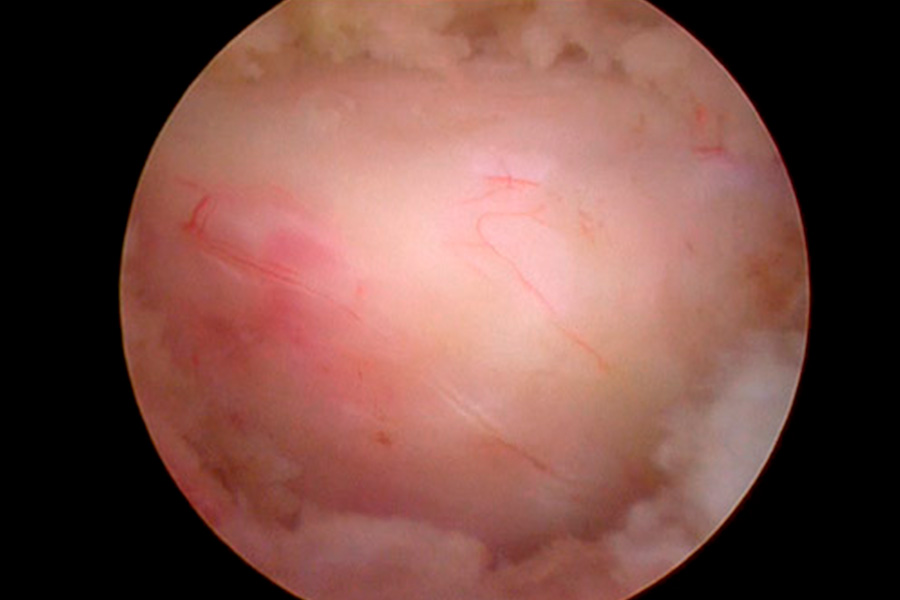

Caso clínico: endoscopia de columna multinivel L4L5 y L5S1

Durante la intervención quirúrgica, se abordarán los dos niveles mediante la técnica de endoscopia de columna.